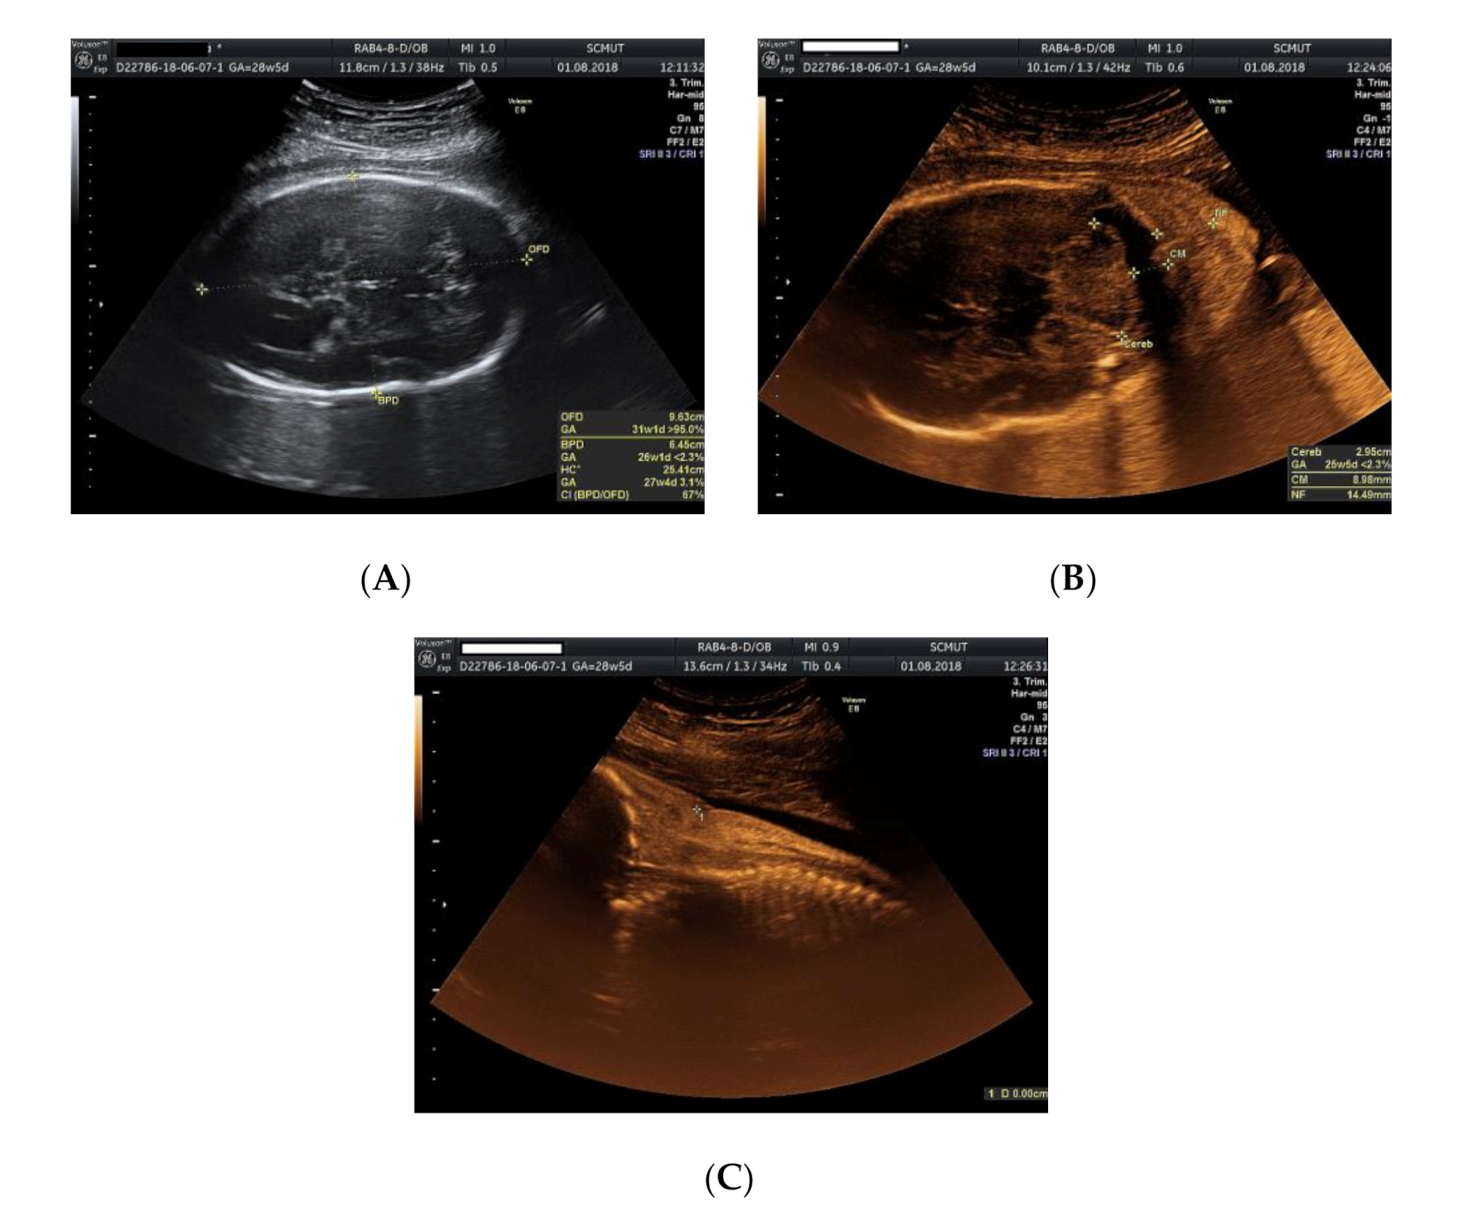

2. Case Presentation